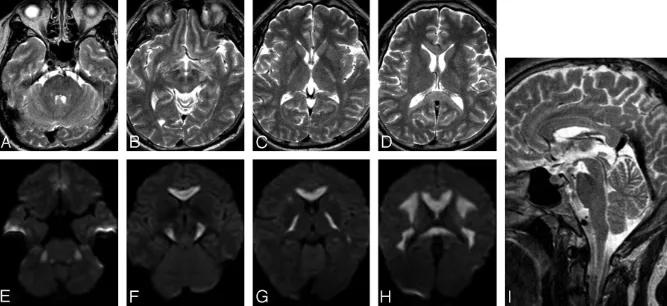

上排:原发性胼胝体变性急性期

下排:原发性胼胝体变性慢性期,表现为胼胝体萎缩、软化

急性期原发性胼胝体变性(胼胝体压部及体部病变,CT呈低密度,T1WI呈稍低信号,FLAIR呈稍高信号,扩散受限)向慢性期转变,慢性期胼胝体压部病灶出现坏死或囊变,FLAIR呈低信号